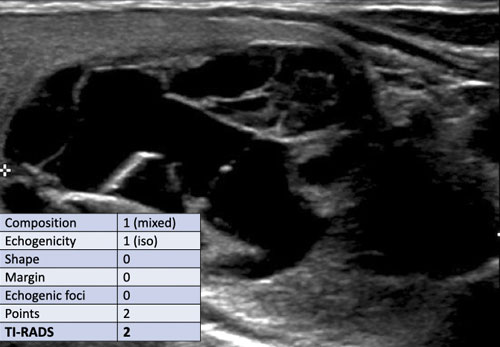

Case 1

Kiểm tra hình ảnh và xác định điểm TI-RADS.

Cuộn hình ảnh để xem điểm TI-RADS.

Nốt này có thành phần hỗn hợp, với thành phần nang nằm ở trung tâm.